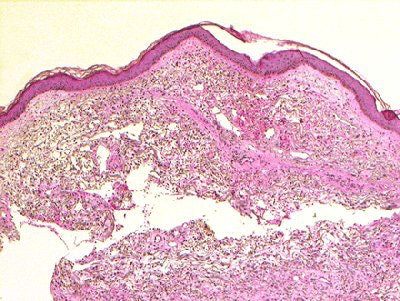

![]() |

| Above, the dermis demonstrates haphazardly arranged collagen bundles and a strikingly increased number of spindled and plump fibroblast-like cells. Below, mucin is frequently present and demonstrable by the colloidal iron alcian blue (pH 2.5) staining methods. Cowper SE. Nephrogenic Fibrosing Dermopathy [NFD/NSF Web site]. 2001-2007. Available at www.icnfdr.org. Accessed 3/5/2007. |